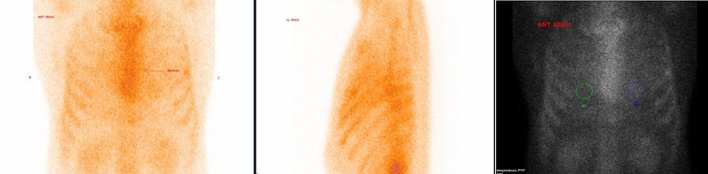

核素心肌显像常用的显像剂是99Tcm-PYP,注射剂量约为20mCi(740MBq),患者检查前无需禁食。

图像评估有2种方式,包括:(一)Perugini可视化评分:0分,心脏无摄取;1分,心脏摄取低于肋骨摄取;2分,心脏摄取等于肋骨摄取;3分,心脏摄取高于肋骨摄取;(二)半定量法:99Tcm-PYP常通过心脏与对侧肺摄取比值(heart-to-contralateral lung uptake,H/CL)。

ATTR-CM的诊断标准为:心脏/肋骨比分级 :2-3 级别以上;心脏/对侧胸部( H/CL )>1.5;达到以上诊断标准,则强烈提示ATTR型心肌淀粉样变。

99Tcm-PYP心肌显像

对诊断ATTR型心肌淀粉样变具有高度的敏感性和特异性,并可能有助于其早期发现,研究报道当心肌摄取为2~3级且血清或尿单克隆蛋白阴性时,对ATTR诊断的灵敏度为97%,特异性为100%。

如图所示

病例一

99Tcm-PYP心肌显像阳性,提示ATTR型心肌淀粉样变(2020 AHA 心脏淀粉样变分级 Grade 3)

病例二

99Tcm-PYP心肌显像阴性,提示心肌淀粉样变证据不足(2020 AHA 心脏淀粉样变分级 Grade 0)【此为正常图像】